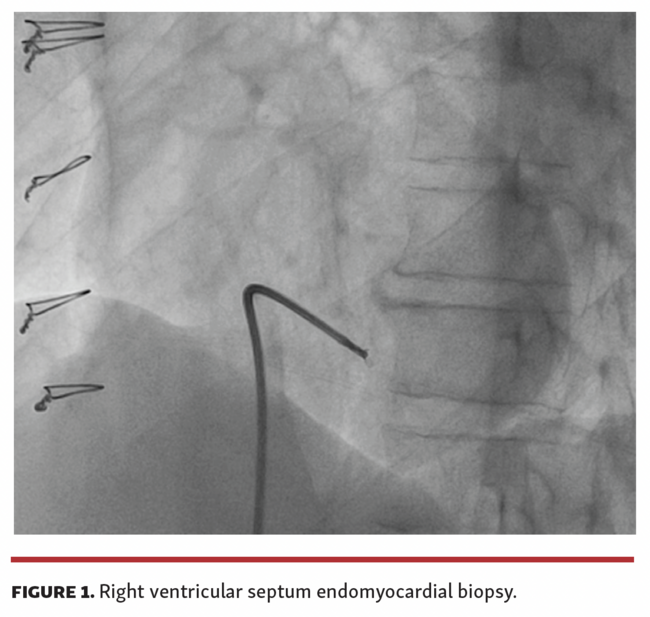

A 69-year-old male patient underwent coronary angiography for evaluation of cardiac ischemia. He had a history of chronic heart failure due to Chagas disease and underwent a heart transplant in 2018. During follow-up, he remained asymptomatic and was regularly subjected to right ventricle endomyocardial biopsies (Figure 1) with no history of graft rejection.